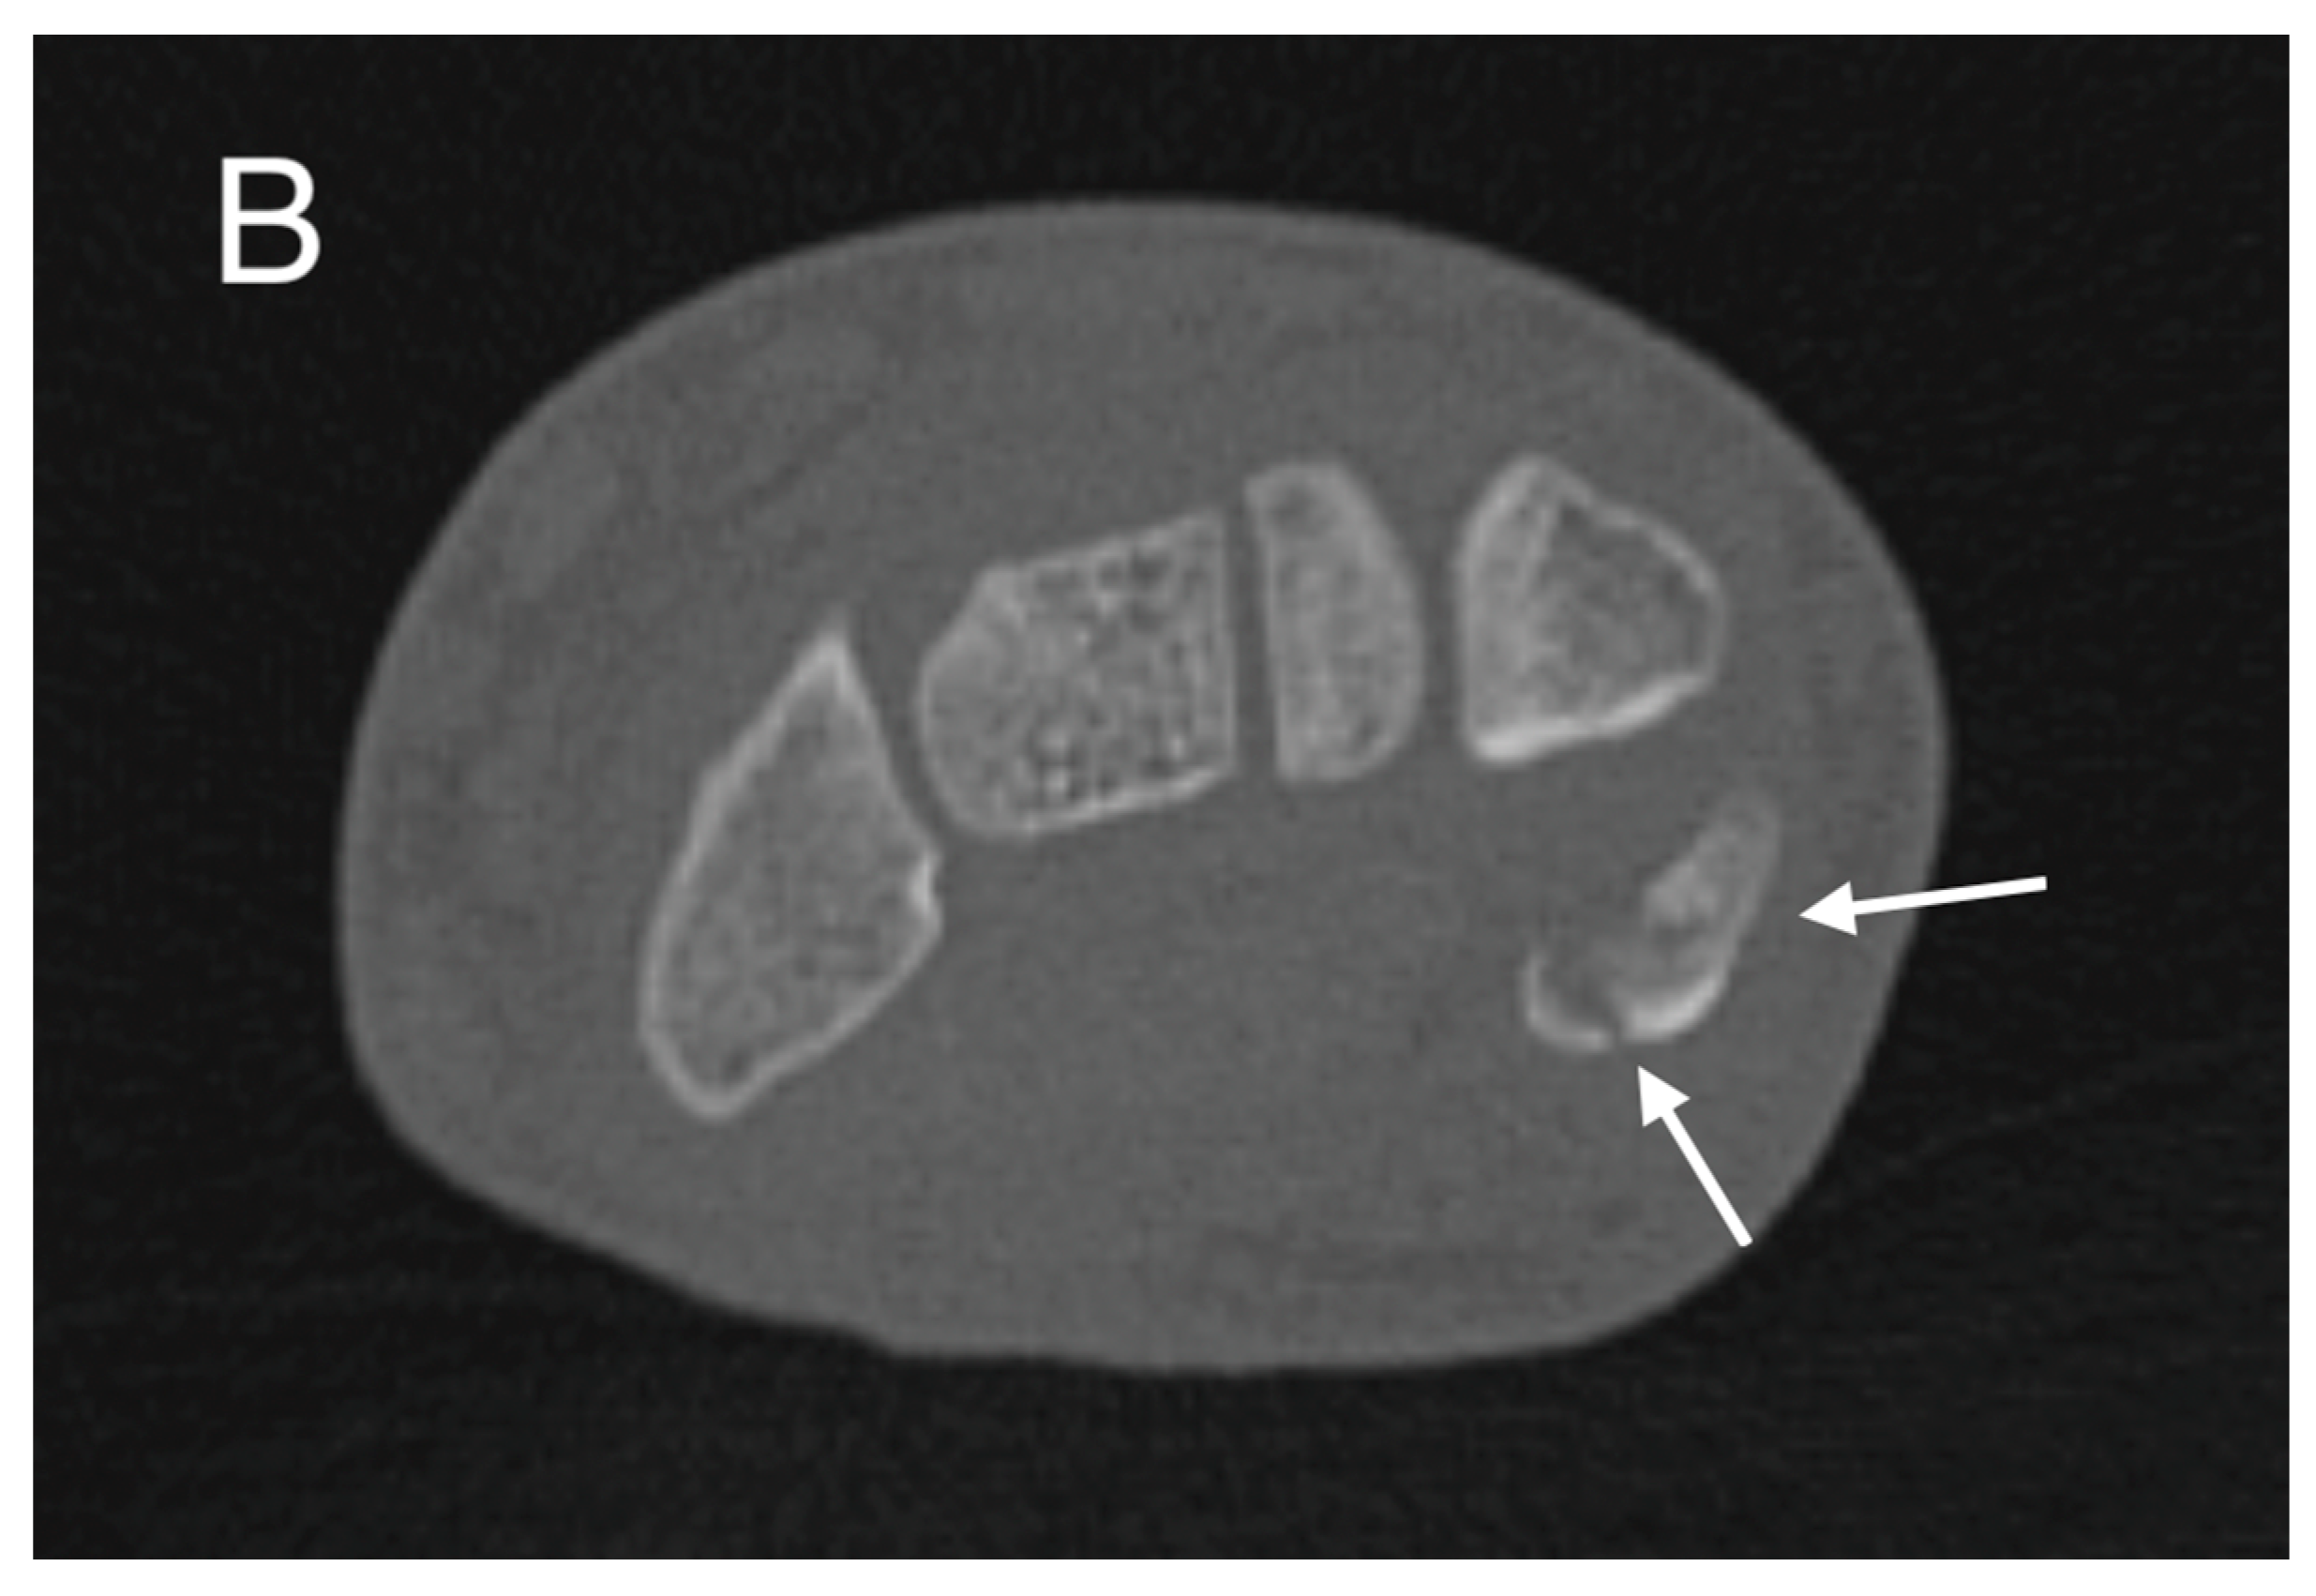

Further confirmation of the dislocation was obtained through subsequent conventional radiographs, specifically utilizing the semi-supination oblique view in a 30° angle (pisiform, pisotriquetral view), with side-by-side comparison of both wrists (Figure 3).

Figure 3.

The semisupination oblique X-ray in 30° angle, side-by-side comparison (L: left, R: right), showing a non-displaced fracture of the pisiform bone (white arrows).